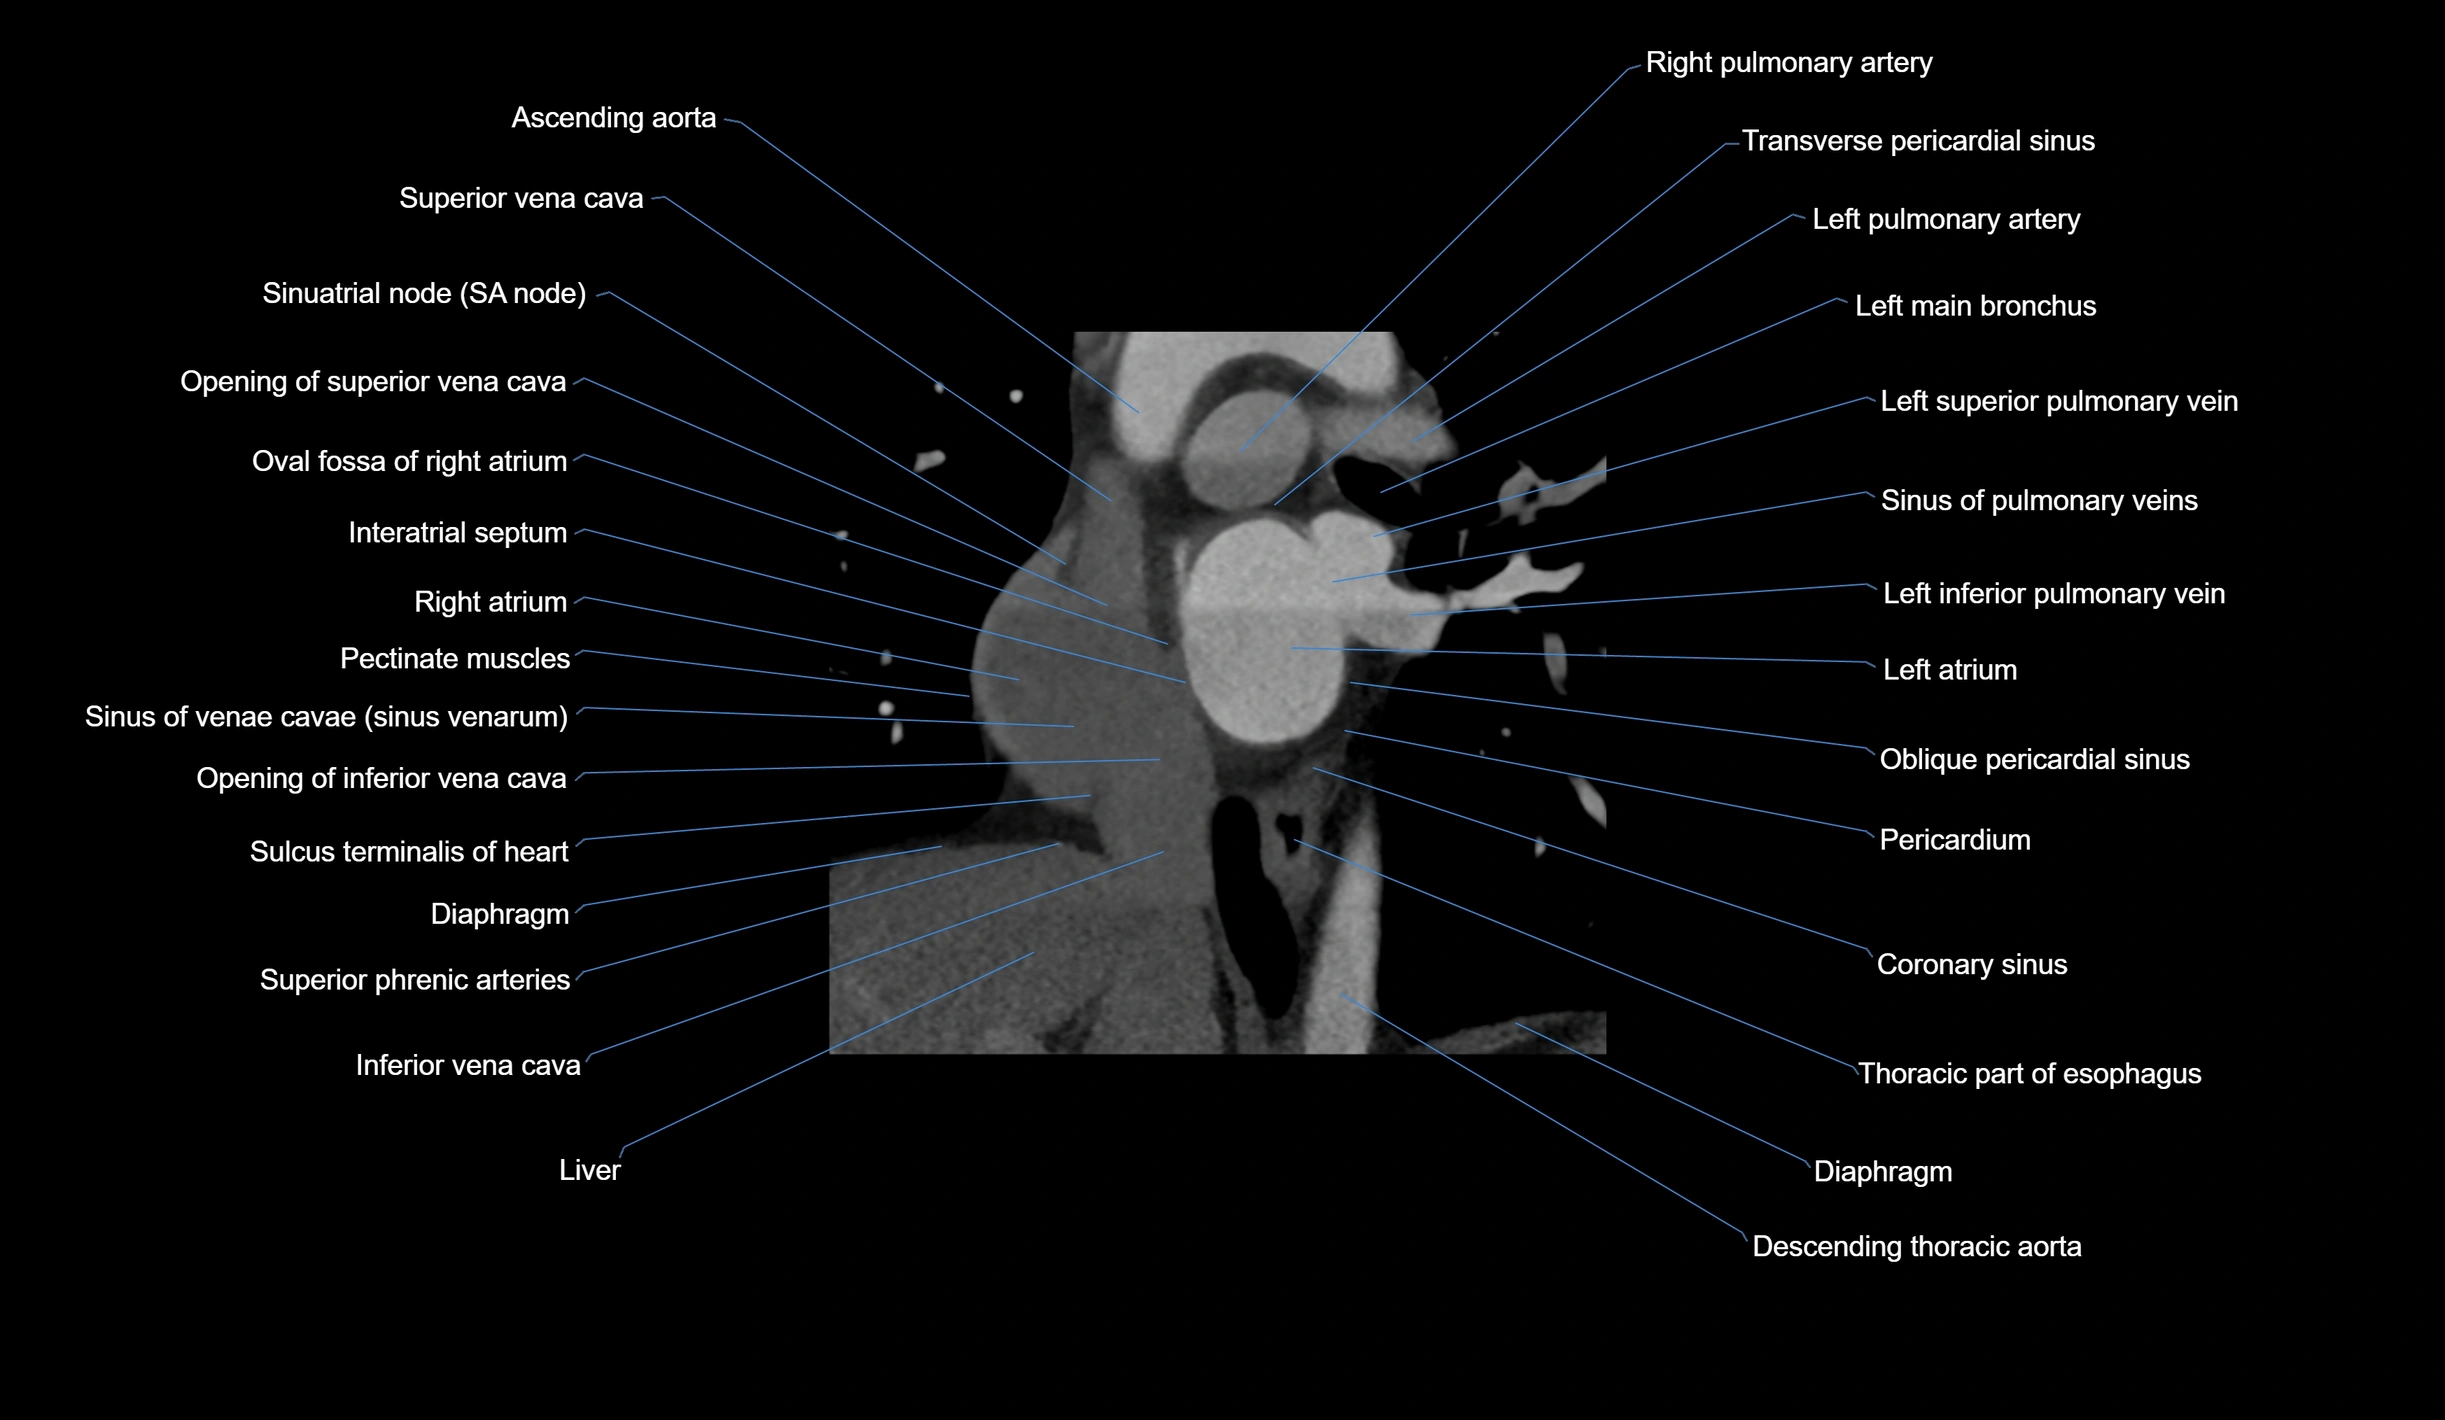

CT images